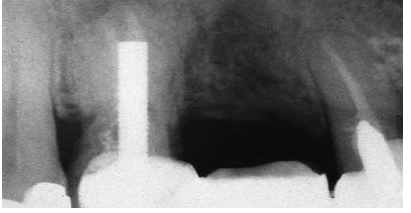

圖1:上頜第二前磨牙根折的根尖片,經(jīng)由預(yù)成金屬樁修復(fù)

盡管短樁從未被提倡使用,但是研究發(fā)現(xiàn)經(jīng)常能在根尖片上觀察到短樁的存在(圖 3)。臨床上發(fā)現(xiàn)在327例樁修復(fù)當(dāng)中,僅僅有34%的樁長度與冠上切-頸長度相當(dāng),即冠與樁長度的比例為1:1。一項(xiàng)研究曾對200例牙髓治療后的牙齒進(jìn)行評估,結(jié)果顯示僅僅14%的樁長度為牙根長度的2/3或者長于牙根長度的2/3。另外一項(xiàng)根尖片研究結(jié)果表明樁修復(fù)中,樁長度為牙根長度的2/3或者3/4的比例僅占5%。當(dāng)臨床上應(yīng)用短樁修復(fù)時(shí),由于高應(yīng)力的原因,牙根常常會發(fā)生折斷,反之,增加樁的長度能夠提高牙根的抗折能力。